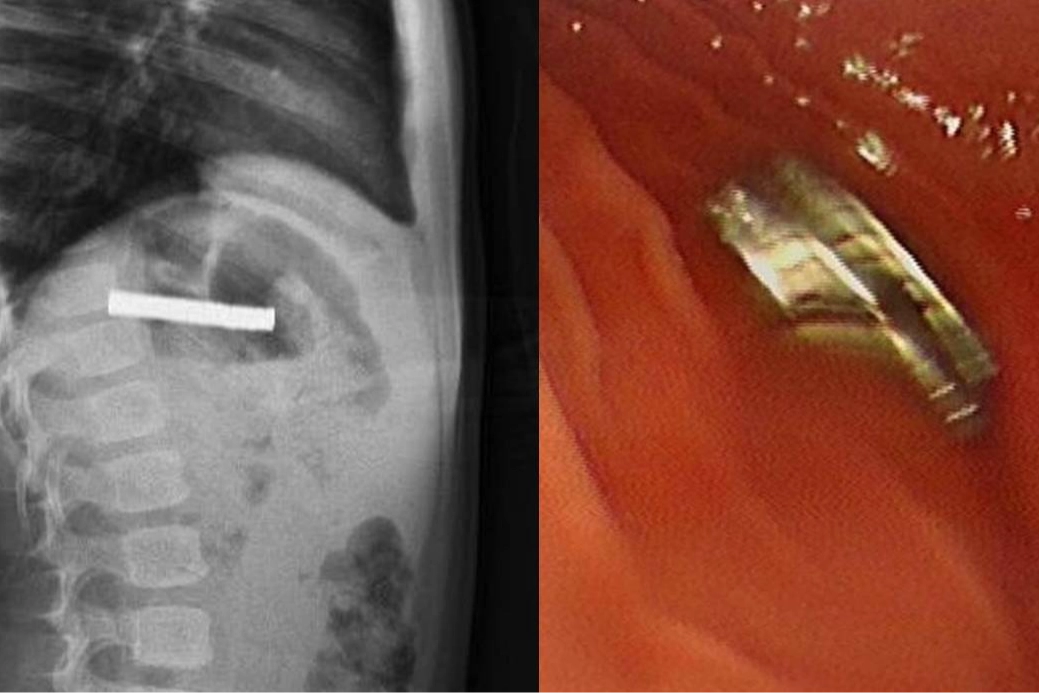

Fırat Üniversitesi Çocuk Gastroenteroloji Hepatoloji ve Beslenme Bilim Dalı Başkanı Prof. Dr. Yaşar Doğan, çocuk hastanın yemek borusuna yapışmış 19 mıknatısı endoskopik yöntemle çıkardı.

Mıknatıslar uzun süre yemek borusunda takılı kaldığı için yemek borusu ve mide girişinde zedelenmeler olurken, çocuğun sağlık durumunun iyi olduğu ve taburcu edildiği öğrenildi.